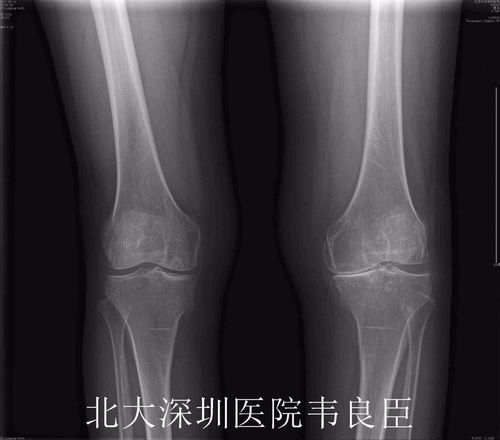

正常膝关节,正常膝关节正位片图片

如图所示,正常膝关节的关节软骨光滑有弹性.

正常膝关节正位片图片

正常膝关节x线图片

正常膝关节x片

正常膝关节x光片